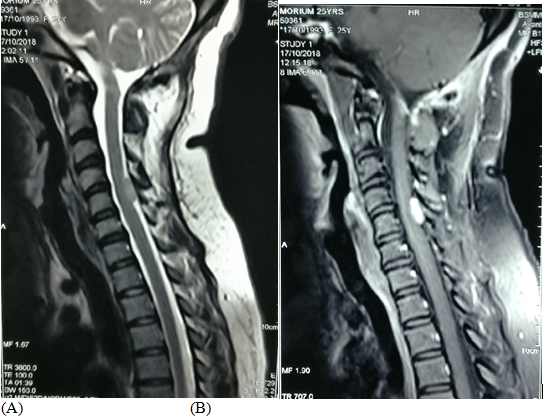

Figure 3(A. T2 sagittal, B & C are contrast sagittal and coronal respectively): post-operative image showing there is no residual tumor at FM.

After proper evaluation he underwent posterior midline sub occipital craniectomy with removal of C1 arch. Gross total removal of tumor was done with Simpson grade I. Tumor was firm in consistency, fibrous, non suckable, moderately vascular. There was pial invasion at the lower part of the medulla. Left sided PICA was severely attached with the tumor which was carefully separated. Dural attachment of tumor was found and involved dura was removed. Duroplasty was done with artificial dura. Post-operative recovery was uneventful. Tissue was sent for histopathology which reveals atypical meningioma WHO grade II. After surgery patients symptoms were improved gradually at 3 months of follow up. He showed marked improvement of power in his all limbs. And he can walk without any support.  Post-operative MRI after 3 months show no residual tumors (Figures 5A-D).

Figure 4Post-operative MRI after 3 months show no residual tumors.